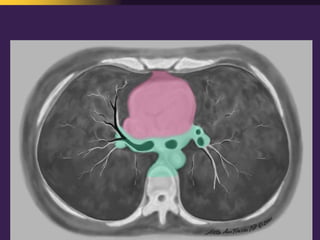

This document discusses mediastinal pathology using a compartmental approach. It describes the anatomy of the mediastinum and divides it into anterior, middle, and posterior compartments. Each compartment contains different structures and has a characteristic distribution of lesions. For example, 50% of lesions occur in the anterior compartment, which contains the thymus. The thymus is the most common site of lesions in the anterior compartment. Thymomas are the most common epithelial tumors of the thymus and mediastinum.